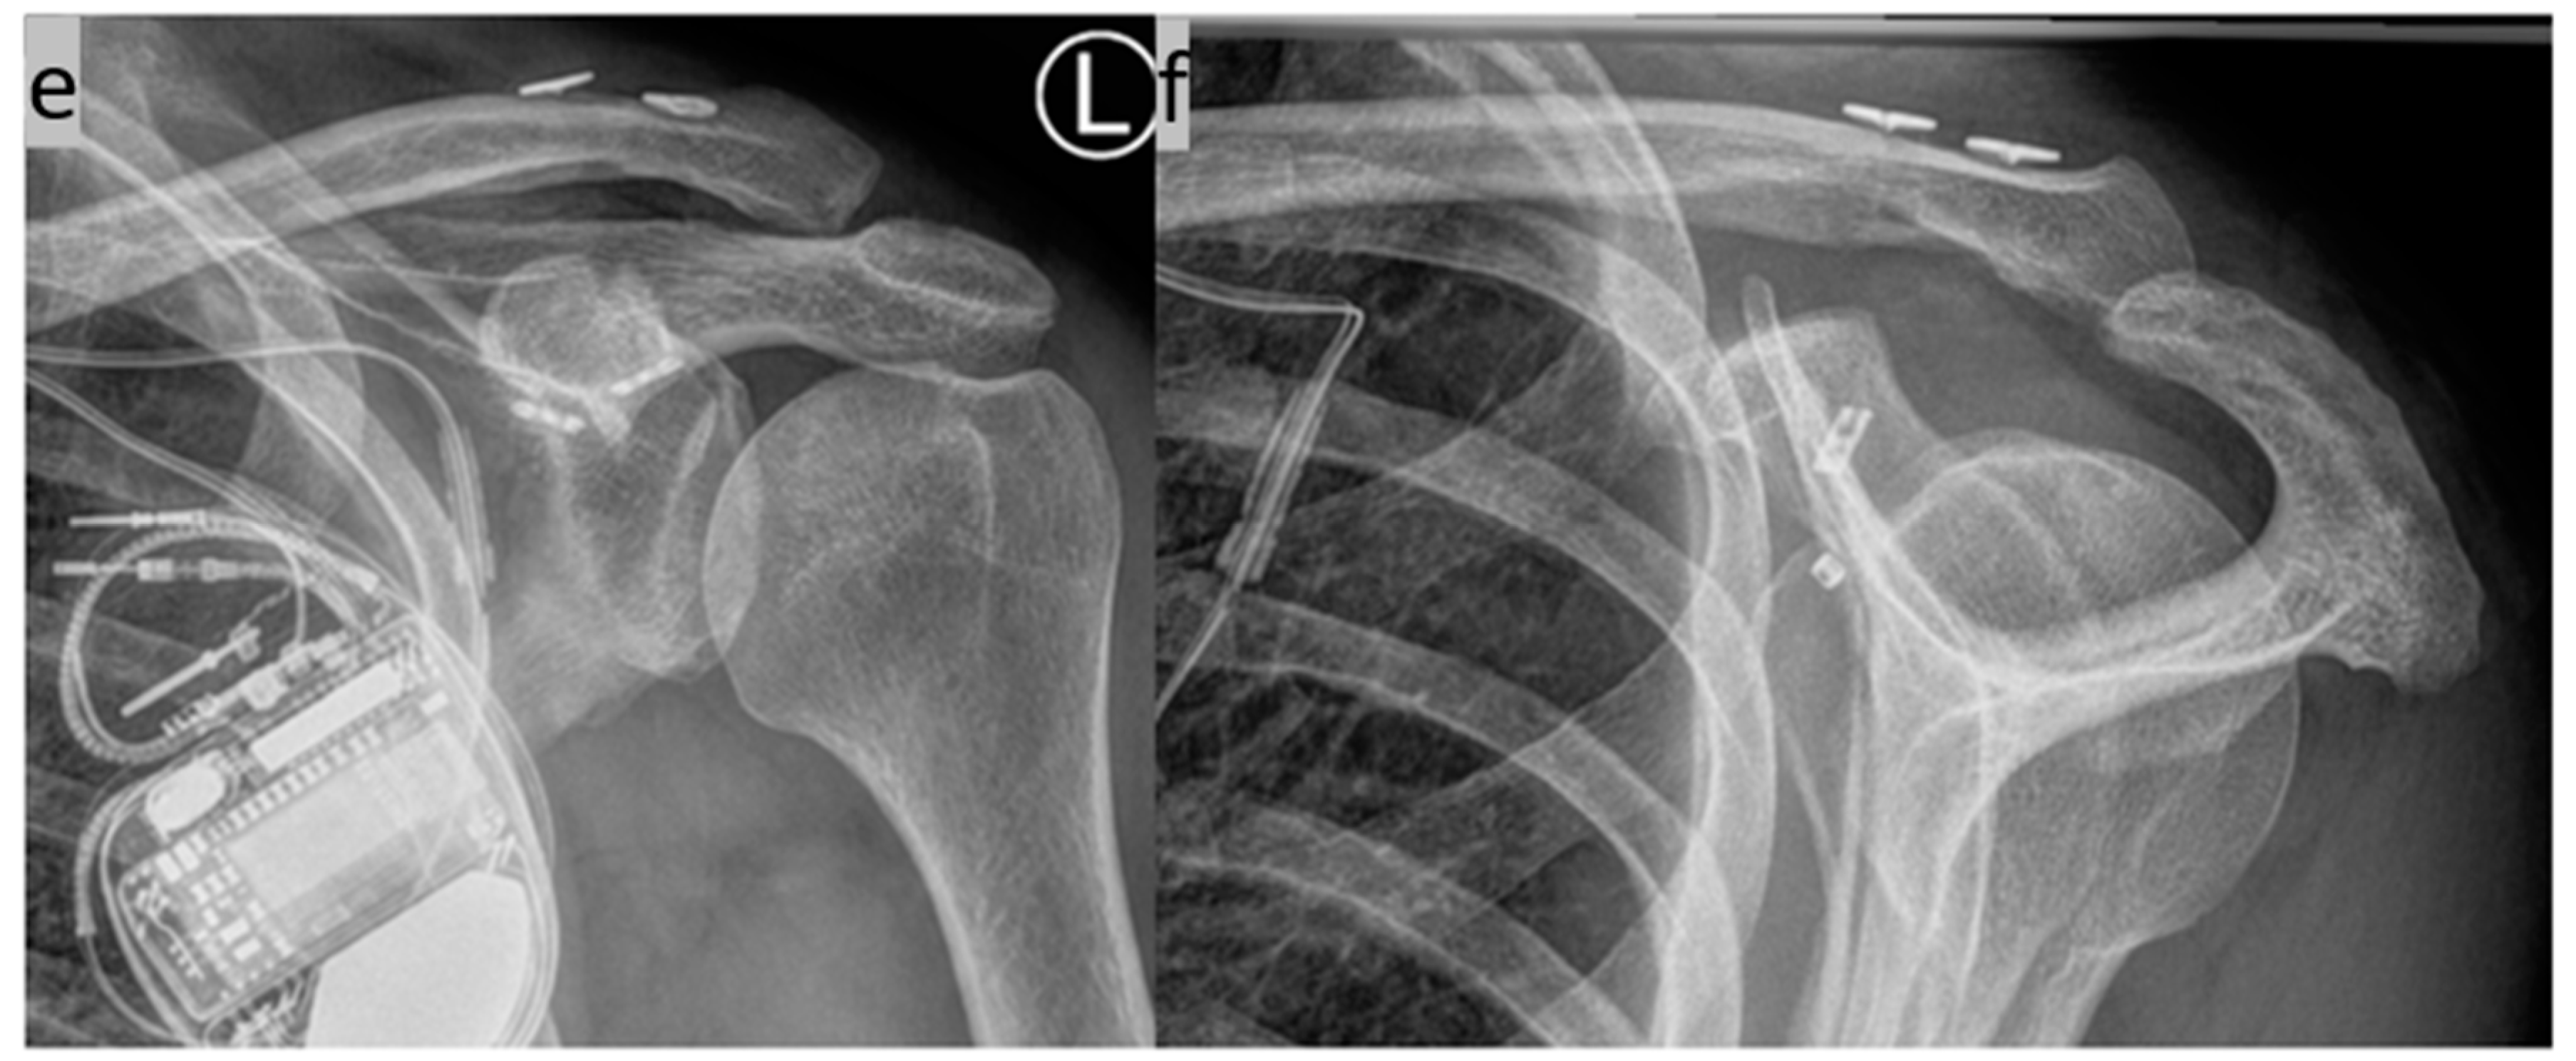

2. Surgical Technique

- Böhringer, A.; Gebhard, F.; Dehner, C.; Eickhoff, A.; Cintean, R.; Pankratz, C.; Schütze, K. 3D C-arm navigated acromioclavicular joint stabilization. Arch. Orthop. Trauma. Surg. 2023, 144, 601–610. [Google Scholar] [CrossRef]